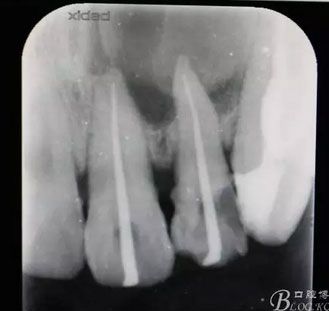

圖2.根管治療術(shù)中試尖影像